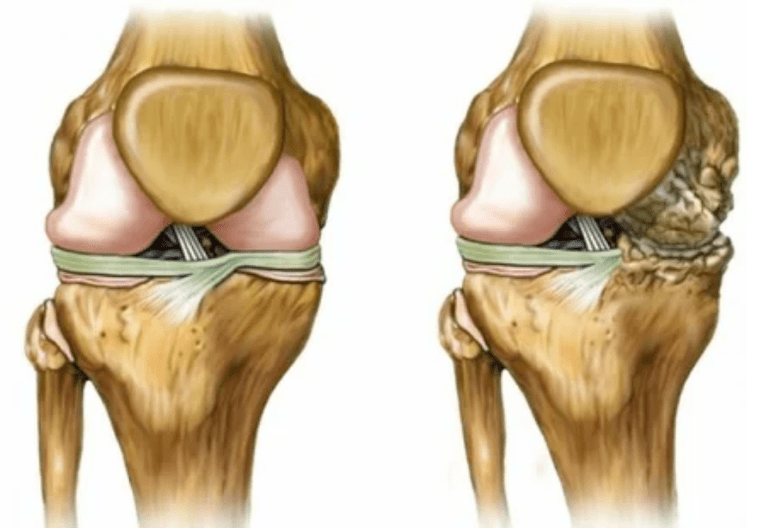

- 1 degree.Disordishes morphological disorders have already begun, but they are still not visible.Pathology mainly affects the condition of synovial fluid, which worse supplies cartilage tissue with nutrients, reducing cartilage strength.The load on the joints provokes inflammation and pain.

- Phase 2. Due to lack of supply, the necessary cartridges are destroyed, bone growths form on the cartilage surface.Pain acquire a more pronounced character, intensify after a long break, eliminated from small physical work.Pain is associated with inflammation.The muscles are stretched, which leads to poor or medium -sized engine -average functions.

- 3 degrees.Often there is pain, it is difficult to move the limb due to changes in the joint.The lesions are wide, they become visible to the bare appearance.The deformation of the common site occurs, the affected area swells and becomes red.The axis axis is disturbed, which leads to the complexity of the movement.Pathological changes provoke the shortening of the ligaments.Contractions appear and appear.The adjacent muscles are shortened or stretched, from which the contractual function is weakened.